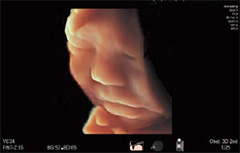

Fetal 3B/4B*

Üç ve dört boyutlu görüntüleme, ailelerle anne karnındaki bebek arasındaki bağlantıyı sağlayan doğum öncesi iletişim olarak rol oynamaktadır. AutoClipper, net bir yüzey canlandırmalı fetal görüntüsü sunarak plasental veya diğer istenmeyen doku sinyallerini çıkararak en uygun kesme düzlemini otomatik olarak belirler.